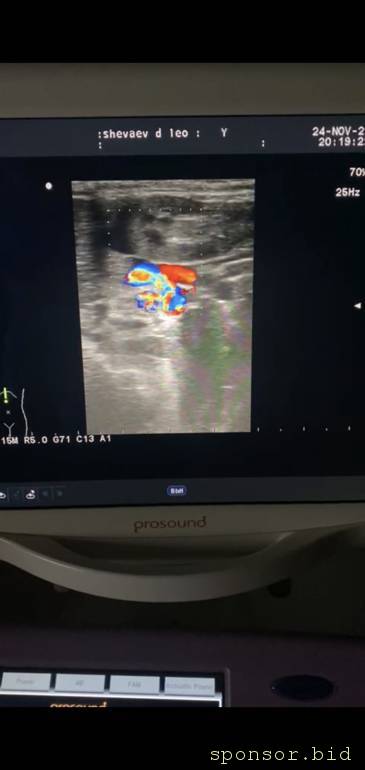

Доброе время суток. Помогите щеночку йорку по кличке Лео мальчик 4 месяца у него диагноз шунт печени. Нужна операция она стоит от 100тыс. Если не сделать в ближайшее время предется его усыпить не возможно смотреть как он страдает. Помогите

Помогите щеночку на операцию - IMG-20221124-WA0001.jpeg